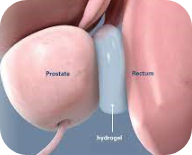

Rectal spacer placement